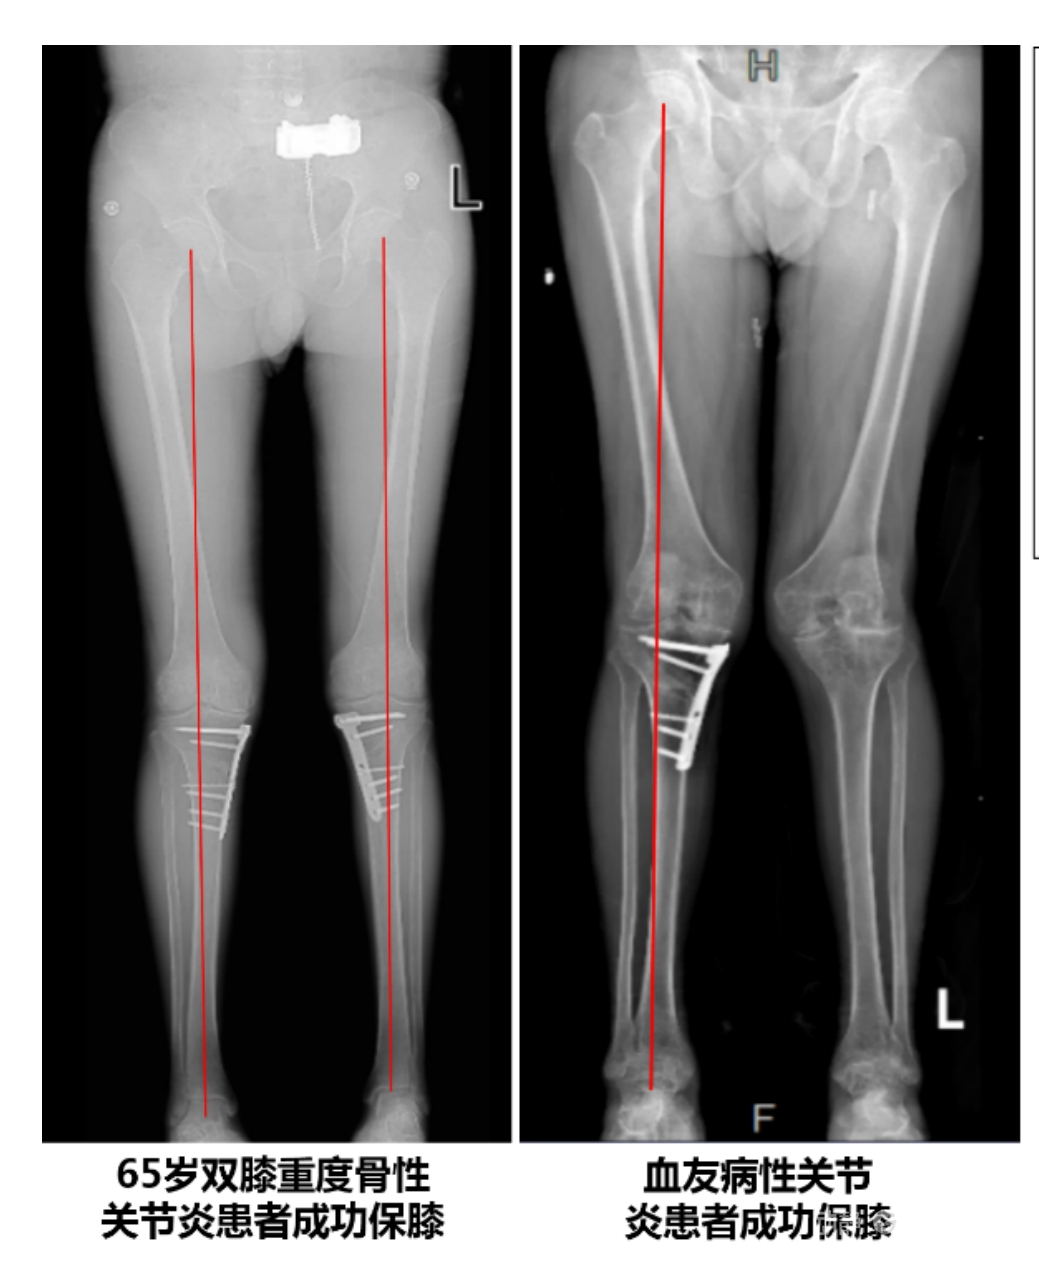

4.2 APTT-HTO脛骨高位截骨術(shù)

該手術(shù)具有經(jīng)皮微創(chuàng)、保留原生膝關(guān)節(jié)結(jié)構(gòu)、符合階梯治療原則等優(yōu)勢,通過調(diào)整下肢力線可促進(jìn)部分軟骨再生,術(shù)后關(guān)節(jié)功能接近正常(如下蹲、爬山),患者還能從事中重體力勞動。相比其他術(shù)式,其有效規(guī)避了髕骨低位、血管損傷、合頁骨折等潛在并發(fā)癥。

目前,APTT-HTO技術(shù)已成功應(yīng)用于千余名患者,幫助保留自身膝關(guān)節(jié)。此類保膝手術(shù)適用于單間室膝關(guān)節(jié)炎患者(如 “羅圈腿”),核心是通過調(diào)整力線糾正畸形,減輕磨損間室壓力、發(fā)揮健康間室作用,延長膝關(guān)節(jié)壽命。若出現(xiàn)膝關(guān)節(jié)疼痛、保守治療無效且X線顯示關(guān)節(jié)間隙部分狹窄,建議及時就醫(yī)評估是否適合手術(shù)。

APTT-HTO脛骨高位截骨術(shù)